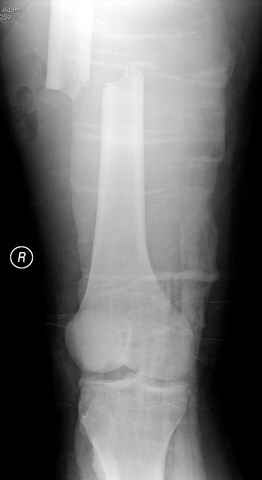

перелом бедра

постоперационные

|